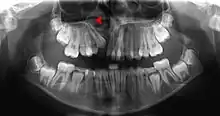

![]() Human jaws with anterior (frontal) portion of alveolar processes cut away towards right | |

The alveolar process (/ælˈviːələr, ˌælviˈoʊlər, ˈælviələr/)[1] or alveolar bone is the thickened ridge of bone that contains the tooth sockets on the jaw bones (in humans, the maxilla and the mandible).[2] The structures are covered by gums as part of the oral cavity.

On the maxilla, the alveolar process is a ridge on the inferior surface, making up the thickest part of the bone. On the mandible it is a ridge on the superior surface. The structures hold the teeth and are encased by gums as part of the oral cavity.[11] Congruent with much of the mandibular canal, the alveolar process comprises cells, nerves, blood vessels, lymphatic vessels, and periosteum.[8] The alveolar crest terminates uniformly at about the neck of the teeth (within about 1 to 2 mm in a healthy specimen).[12][13]